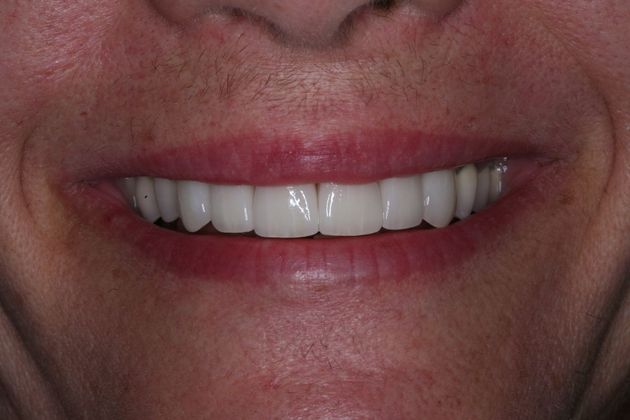

Procedures; TMJ CAT scan, TMJ deprogramming, whitening, sedation dentistry, reconstruction of all the back and upper front teeth with porcelain crowns, bite guard therapy. This foster care provider wanted to be free of the pain in her jaw joints. She had a lifelong history of grinding, many of her back teeth were breaking down and her bite was off. Her treatment was performed in sections to spread out the cost. She and her husband were so pleased with the result!